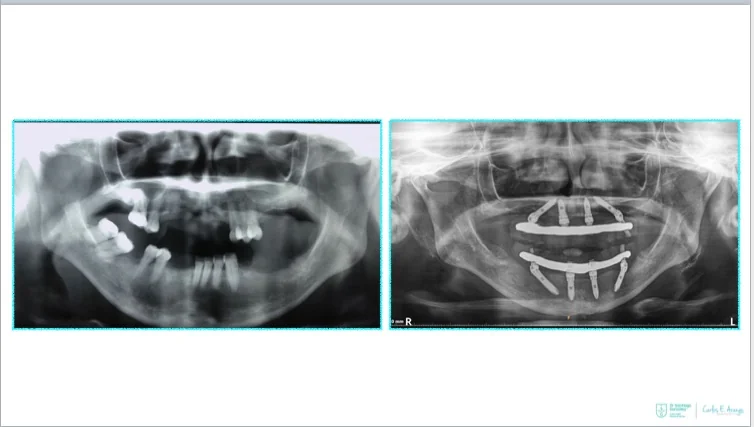

- Full-arch rehabilitation with only four implants

Two straight anterior implants and two implants tilted up to 45º in the posterior - Immediate Function (fixed provisional bridge)

For patients meeting criteria for immediate loading of implants - Graftless Procedure: Bone grafting is avoided by tilting the posterior implants, utilizing available bone.